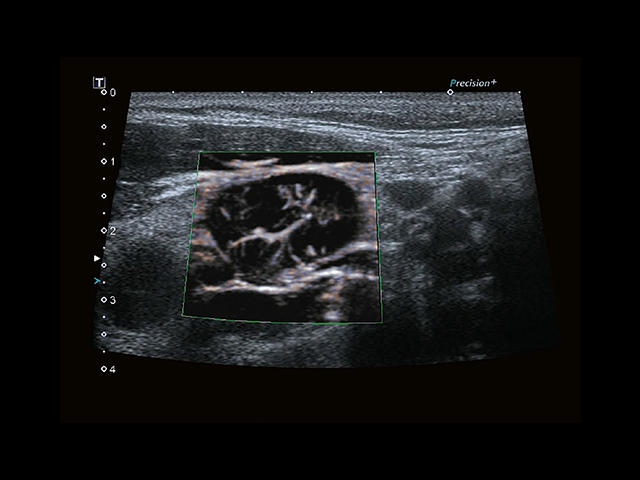

Обновленная версия легендарного УЗ-сканера. Стационарный аппарат экспертного класса Aplio 500 Toshiba NEW, визуализирует анатомические структуры в высоком разрешении. Модель позволяет выявить микрокальцификаты, новообразования, нарушения в работе сердца, сосудов и мышц. Присутствует функция виртуальной эндоскопии, 4D-сканирования, эластометрии тканей, УЗИ с контрастированием. За повышение качества изображения отвечают технологии ApliPure и Superb Microvascular Imaging. Первая задействует возможности пространственного и частотного кодирования, формирует цельный визуальный ряд с сохранением клинических маркеров. Вторая улучшает отображение микрососудистого русла, используя доплеровский эффект. Модель оснащена 21-дюймовым монитором, имеет 4 активных порта. Возможно подключение педиатрических, интраоперационных, лапароскопических и чреспищеводных датчиков.

• SMI. Опция, упрощающая визуализацию микроциркуляторного русла. С ее помощью обследуются сосуды с низкой интенсивностью кровотока, изучаются наиболее тонкие структуры. SMI упрощает диагностику новообразований, минимизирует вероятность ошибки.